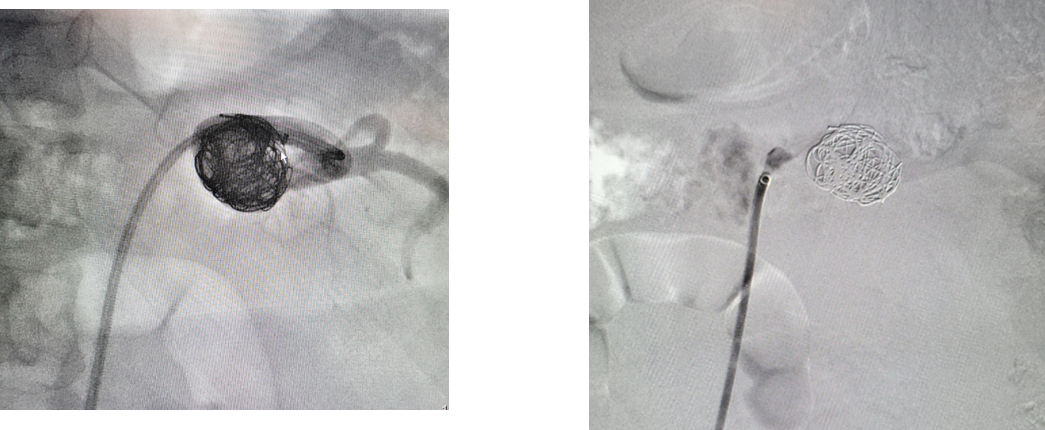

病例3 瘤腔栓塞加胶填充

病例4 两端栓塞+瘤腔填塞

病例5 多发动脉瘤分支+主干栓塞

图为:分支栓塞